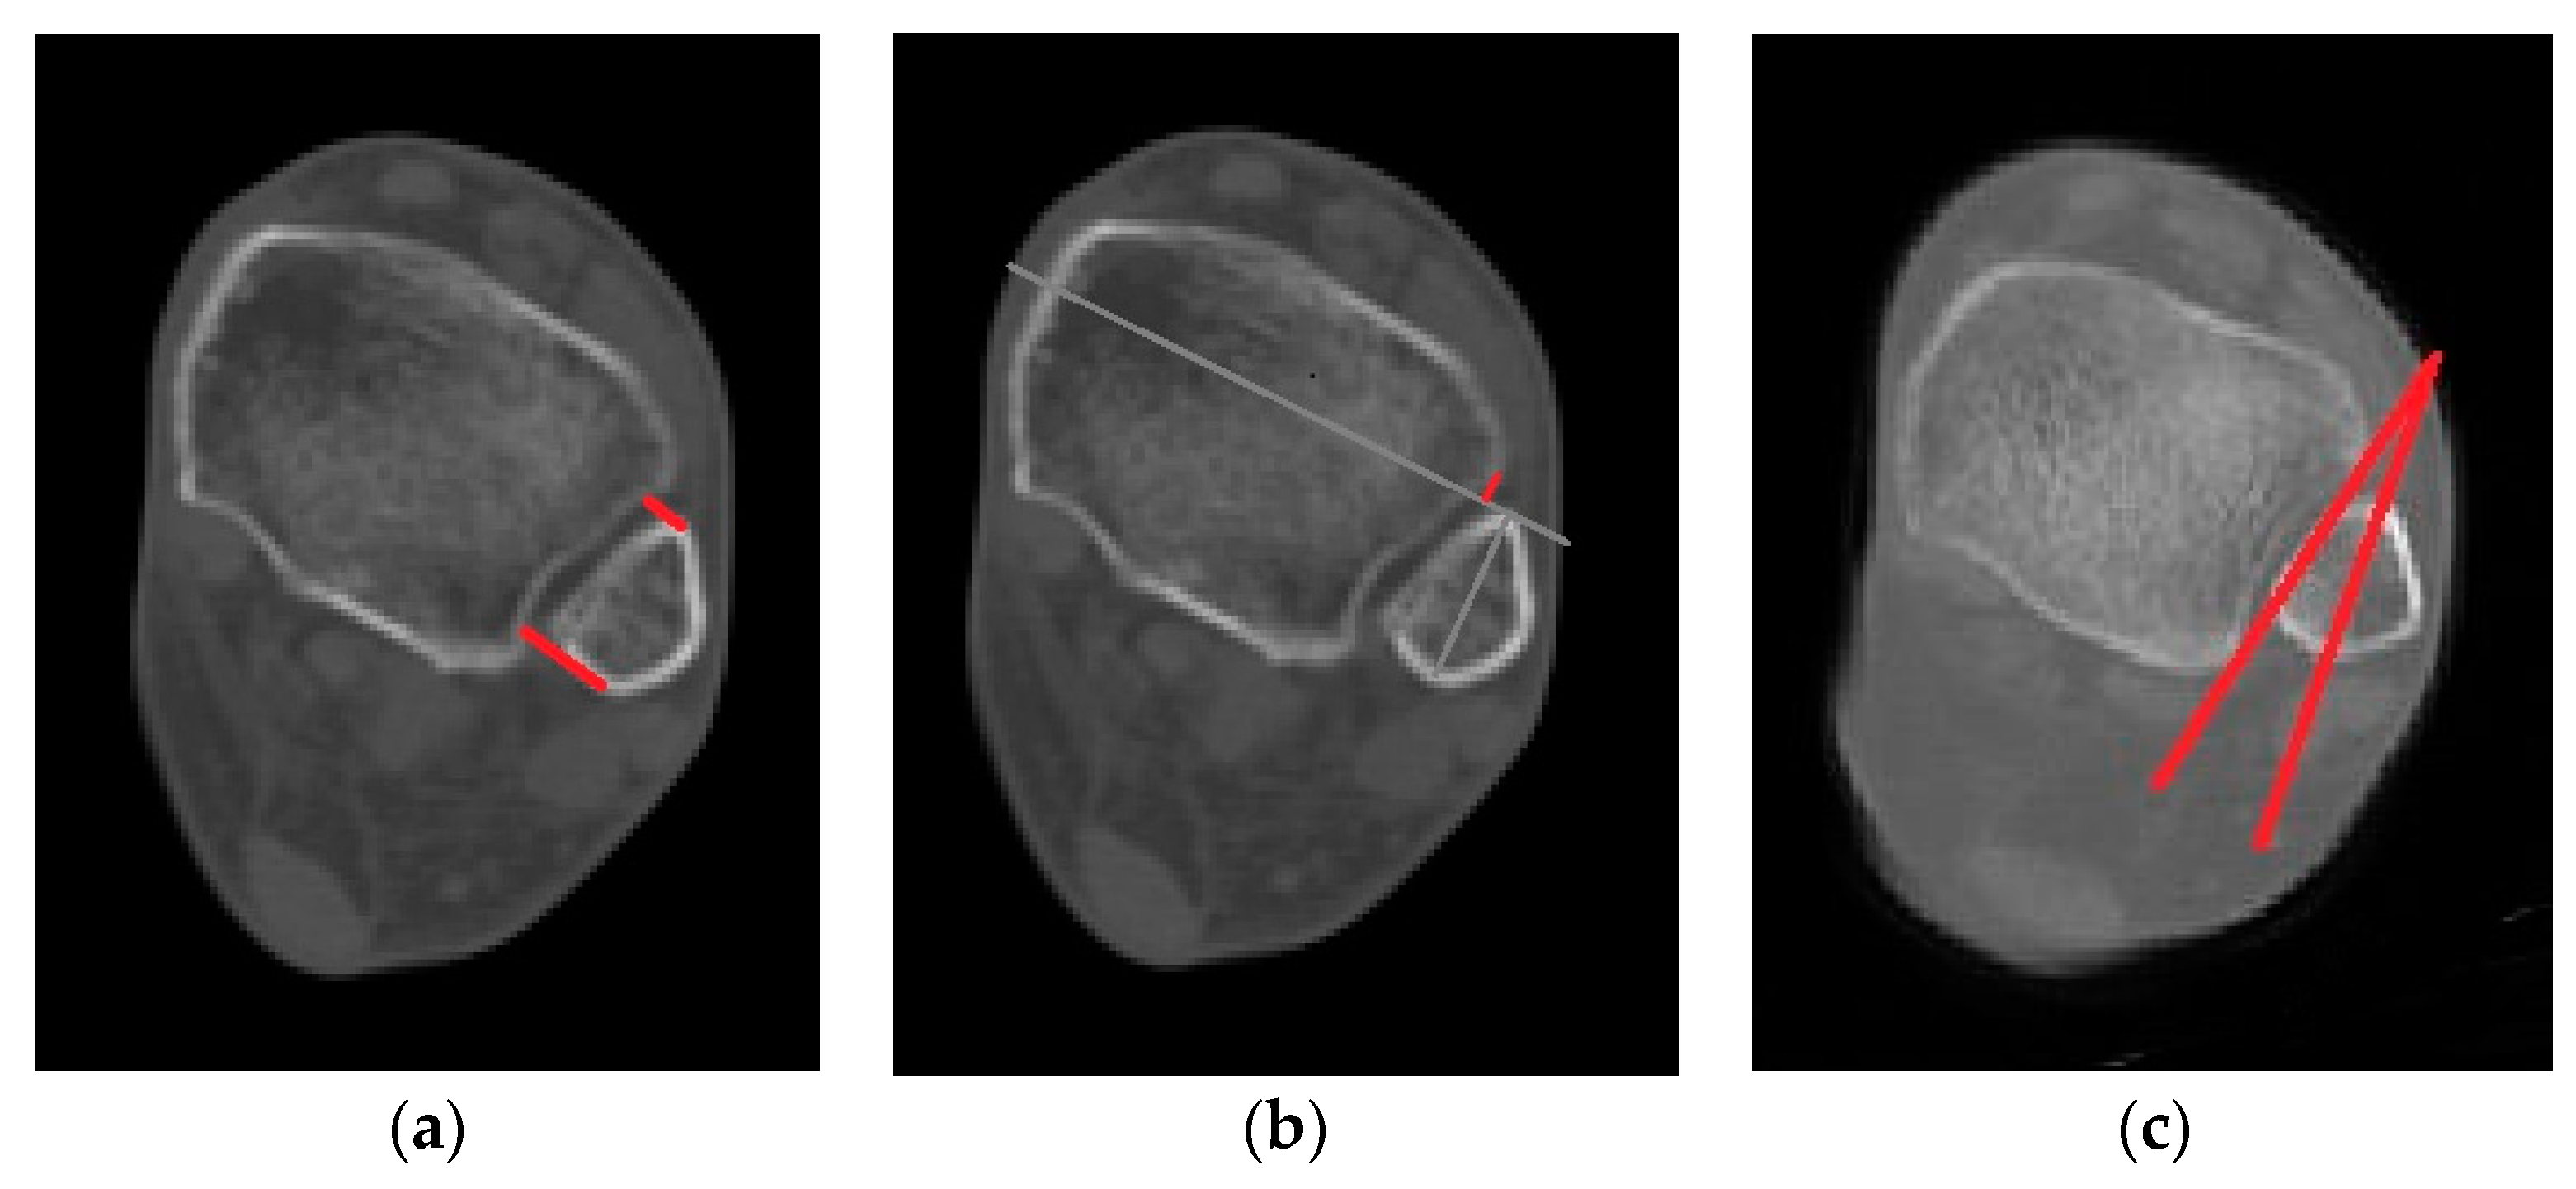

2.3. Radiological Evaluations

This study evaluated syndesmosis reduction by analyzing postoperative axial CT images captured 1 cm proximal to the tibial plafond (Table 1 and Figure 1) [16,17,18,19]. Four radiographic measurements were chosen and assessed with a PACS image viewer software (Dejaview2 version 1.0, Dongwun Information Technology, Republic of Korea). Two independent observers, blinded to patients’ clinical outcomes and current complaints, objectively evaluated the measurements. The process was repeated after a 6-week interval to ensure reliability.

Figure 1. Radiologic measurements. (Red line) (a) Direct anterior difference and direct posterior difference. (b) Fibular translation. (c) Fibular rotation (Red line).